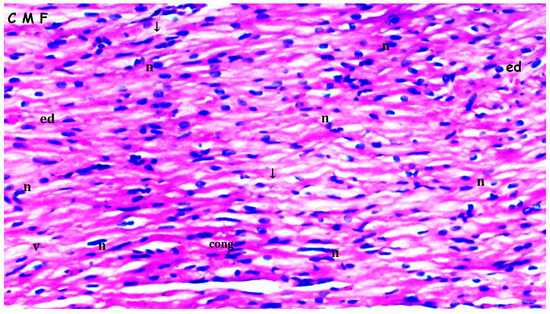

3.1. Histopathologic Findings

| [23,33] Myocardial disorganization | 0.50 ± 0.22 | 0.50 ± 0.22 | 1.25 ± 0.16 *,& | 0.63 ± 0.18+ | 0.028 |

| Inflammation and neutrophil infiltration | 0.33 ± 0.21 | 0.50 ± 0.22 | 1.25 ± 0.16 *,& | 0.63 ± 0.18+ | 0.012 |

| Interstitial fibrosis | 0.33 ± 0.21 | 0.50 ± 0.22 | 1.25 ± 0.16 *,& | 0.75 ± 0.16 | 0.010 |

| Interstitial edema | 0.33 ± 0.21 | 0.50 ± 0.22 | 1.25 ± 0.16 *,& | 0.63 ± 0.18 + | 0.012 |

| Swelling of myocardial cells | 0.33 ± 0.21 | 0.33 ± 0.21 | 1.13 ± 0.13 *,& | 0.63 ± 0.18 + | 0.013 |

| Myocardial necrosis | 0.17 ± 0.17 | 0.33 ± 0.21 | 0.75 ± 0.16 | 0.63 ± 0.18 | 0.126 |